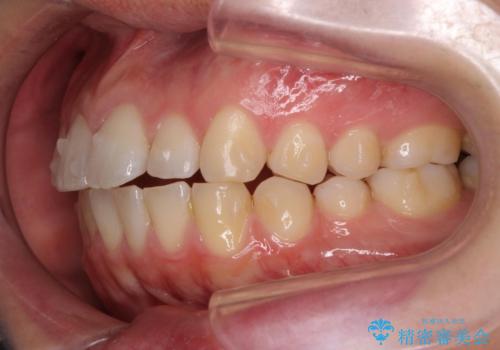

前歯が気になる。インビザラインライト

- 前歯が気になるとの事で来院。

矯正を希望されたが費用と時間を抑えたいとの事でインビザラインライトで矯正を行いました。(奥歯の位置関係はほぼ変えない)

前歯が綺麗に並び大変満足して頂けました。